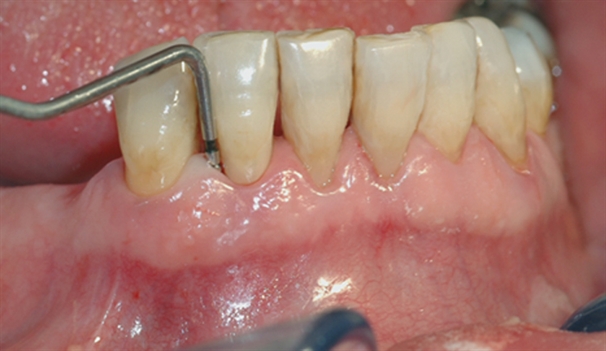

perio stor 2

En undersøkelse med lommeregistrering avdekker likevel et omfattende bentap ved den ene tannen.

perio stor 3

Instrumentet er her lagt utenfor tannkjøttet for å vise hvor stort festetapet egentlig er.